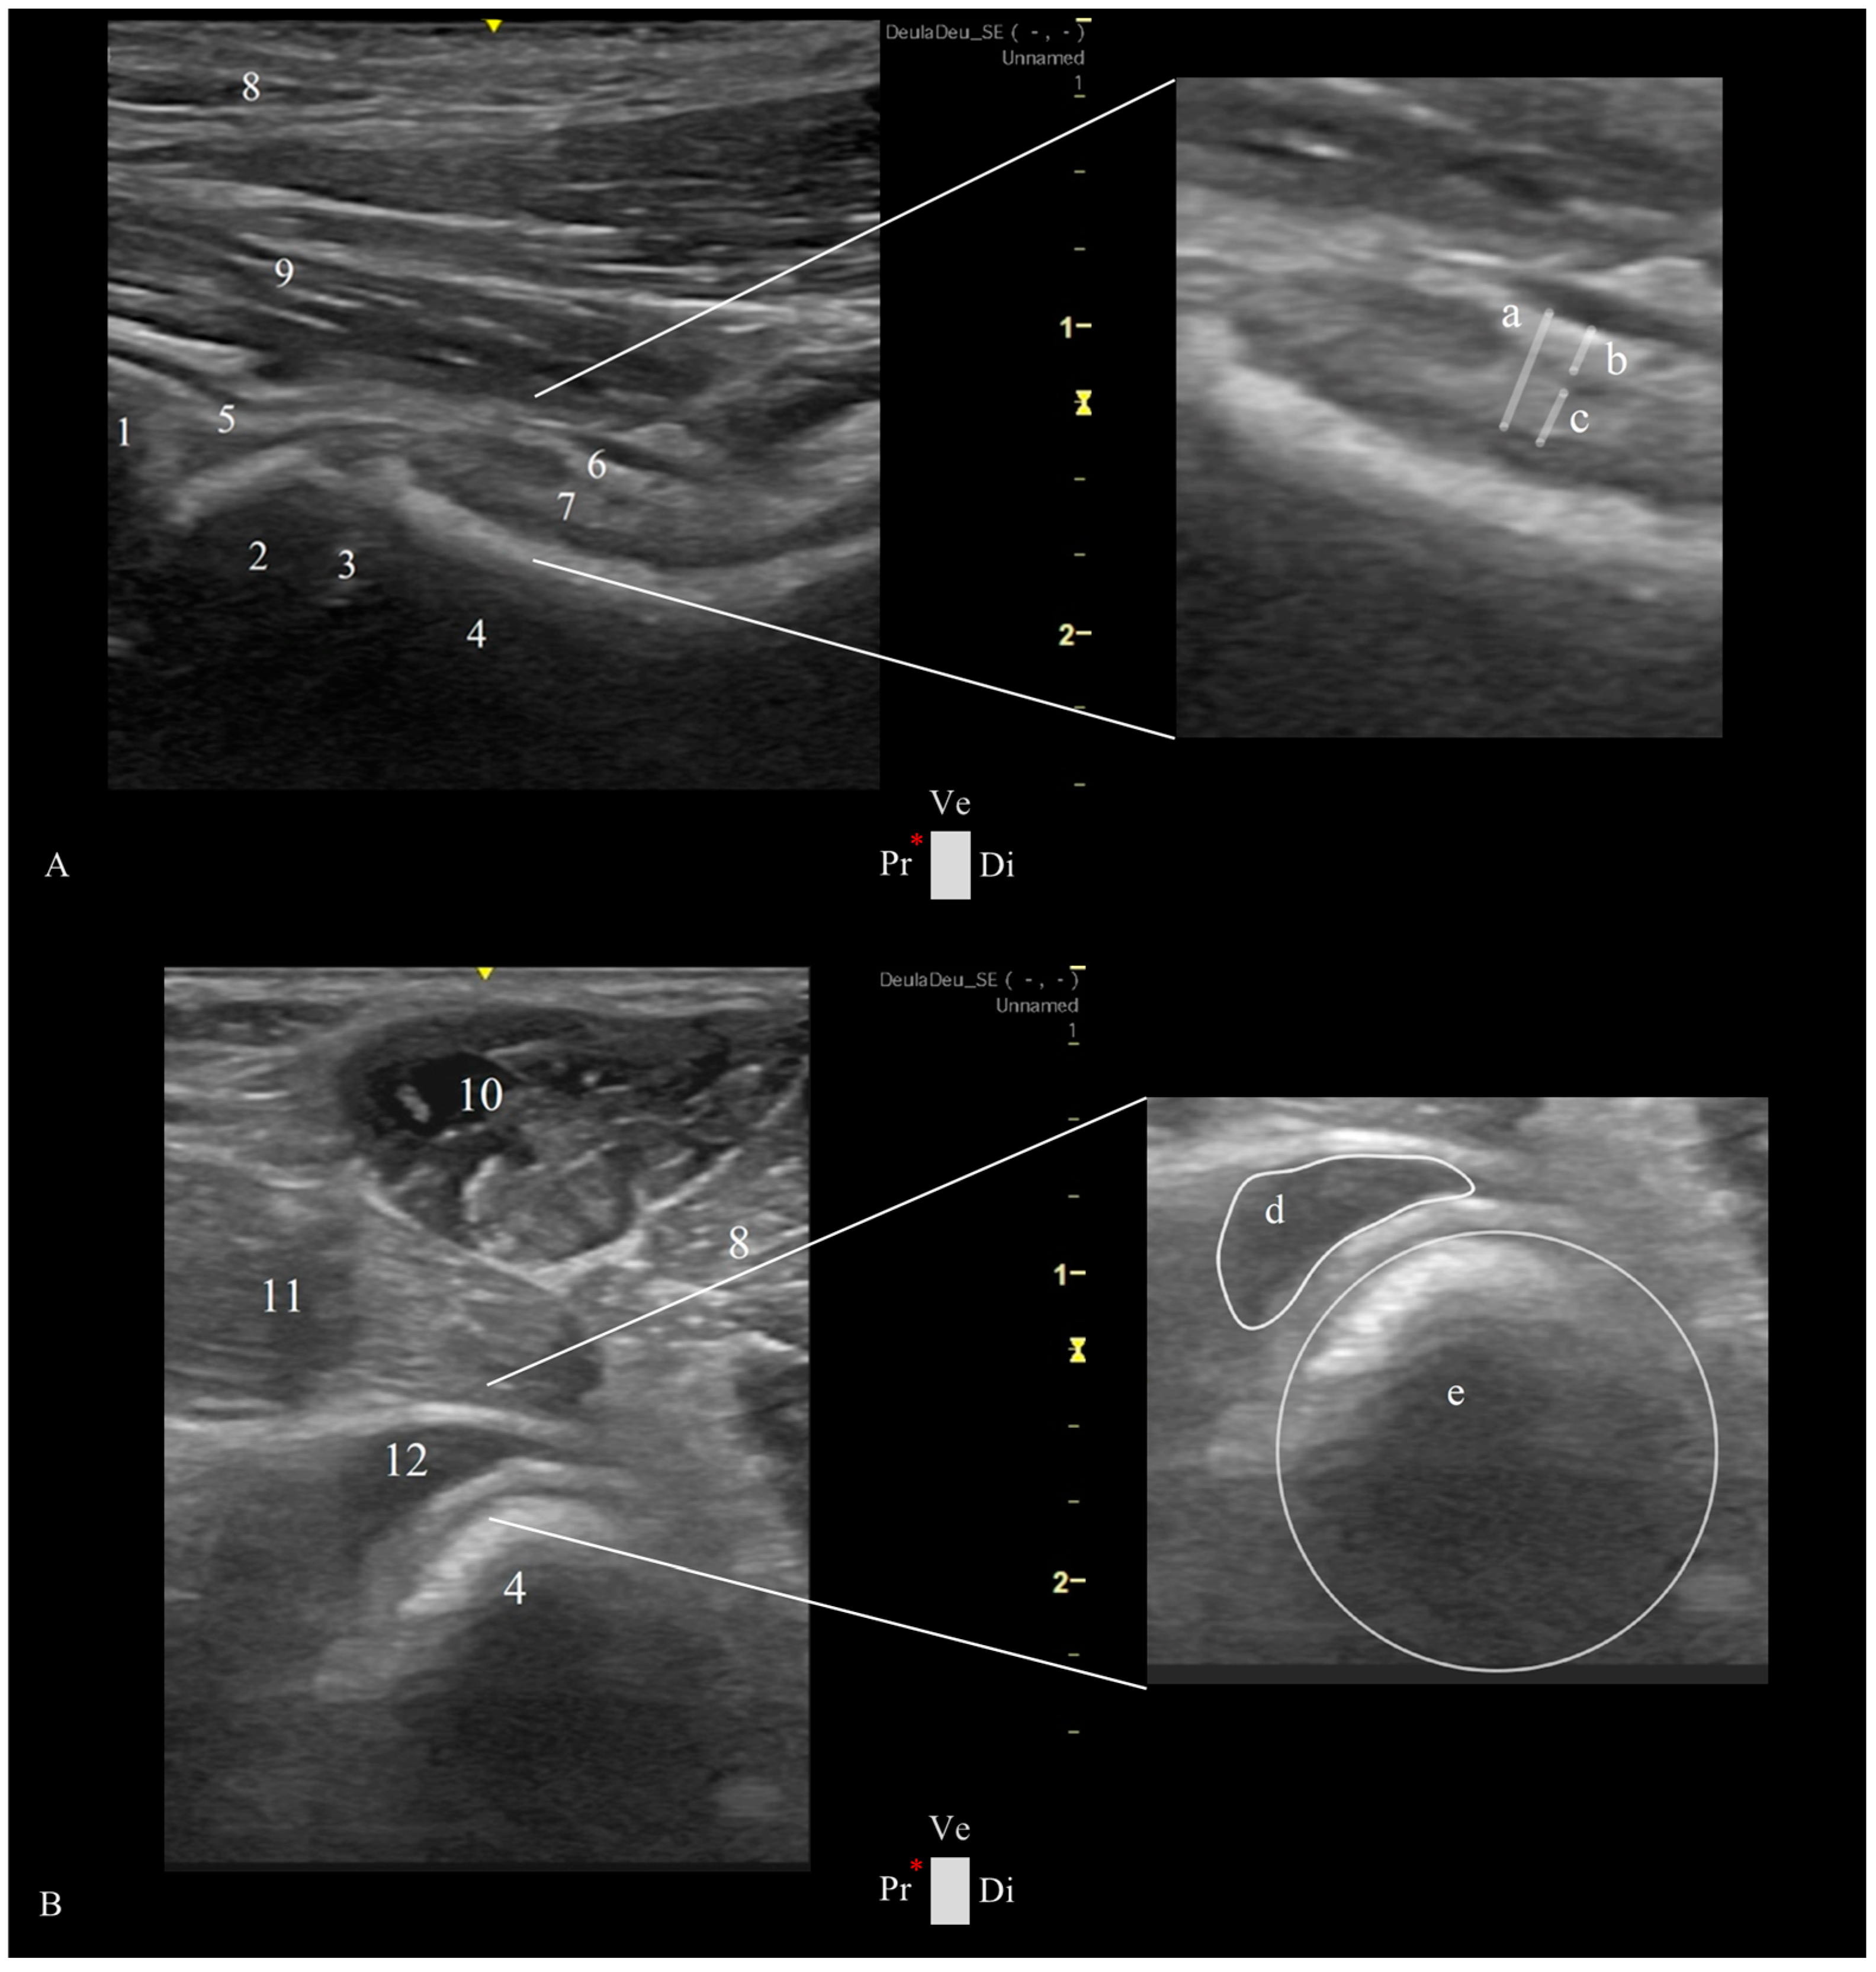

- Longitudinal Femoral Head–Neck Plane

- Transverse Femoral Head–Neck Plane

2.4. Ultrasonographic Hip Joint Measurements